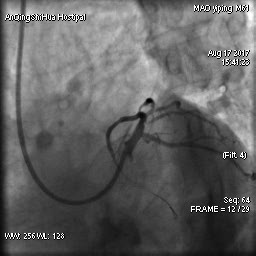

由于毛先生的病變涉及主干分叉,即復雜的真性分叉病變,為保證分支開口得到良好的開放,術(shù)者采取了操作復雜的雙支架術(shù)式,先后運用掏支架網(wǎng)眼、球囊擴張、雙球囊對吻擴張、POT技術(shù)等,實現(xiàn)了完全血運重建。術(shù)后,毛先生的嚴重心絞痛終得緩解。

術(shù)后 心臟左主干末端狹窄解除,血流通暢